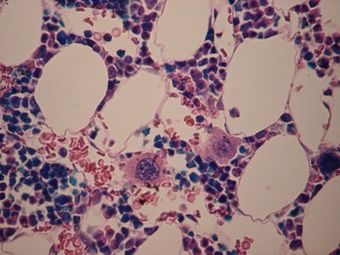

الخلايا النواء في نخاع العظم | |

خلية نواء Megakaryocyte هي أحد خلايا نخاع العظم وهي المسؤولة عن إنتاج الصفائح الدموية اللازمة لعملية التخثر. وتشكل خلية النواء ما يقارب ١ لكل ١٠٠٠ من خلايا نخاع العظم.

خلية النواء هي أكبر خلايا نخاع العظم حجماً بقطر يتراوح بين 5٠ -١٠٠ ميكرومتر (μم)، أي ١٠-١5 ضعف حجم كرة الدم الحمراء. ولخلية النواء القدرة على مضاعفة عدد الدنا دون انقسام الخلية مما يجعل حجم النواة كبير مقارنة بالحجم الكلي للخلية. وقد يصل عدد الرنا إلى ٣٢ ضعف العدد الطبيعي في الخلايا الأخرى (64 N).